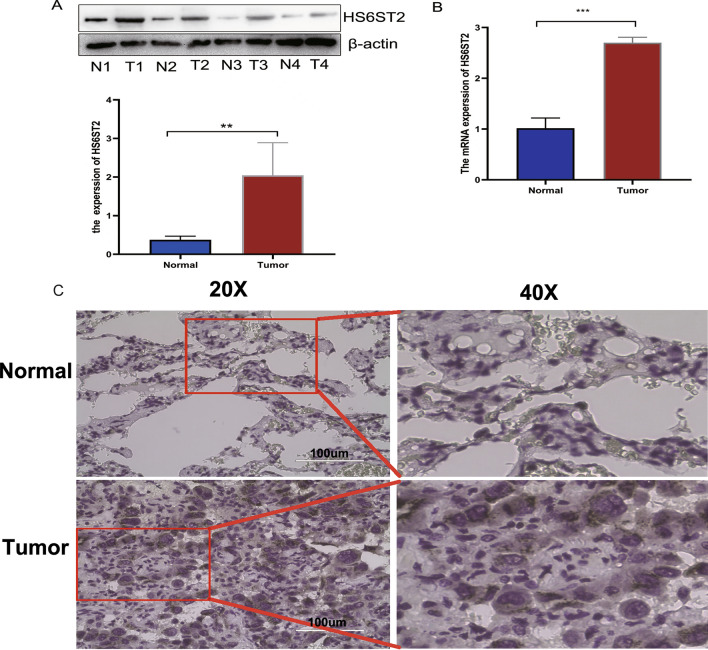

Clinical samples

Fifty matched samples of LUAD and surrounding normal tissues were obtained at the Third People’s Hospital in Yancheng. Among them, there were 32 males and 28 females, none of whom had received radiation or chemotherapy. Out of the total, 24 were smokers. The diagnosis was confirmed using histopathological methods. There were 19 patients in stage I, 15 patients in stage II, 12 patients in stage III, and 4 patients in stage IV. After the tissues were surgically removed or obtained through bronchoscopy, the specimens were frozen in a refrigerator at − 80 °C for future research. All fifty patients provided written informed consent, This project was approved by the Ethics Committee of the Sixth Affiliated Hospital of Nantong University (Approval Number: LS20150413). All experiments were conducted in accordance with the Helsinki Declaration, and informed consent was obtained from all participants.

Reverse transcription-polymerase chain reaction (RT‒qPCR)

We extracted RNA from fresh tissue samples using the Trizol method. The isolated RNA was then reverse transcribed into cDNA using a reverse transcription kit provided by a Chinese genetic engineering company. The PCR reaction mixture was placed in a thermal cycler and subjected to specific temperature and time conditions for PCR amplification. The process involved an initial denaturation step to separate the DNA strands, an annealing step to allow the primers to specifically bind to the template DNA, and an extension step for the polymerase to synthesize new DNA strands. A total of 45 cycles were performed, and the maximum system volume was 20 μl. The ANanoDrop3000 (Thermo Fisher Scientific, Waltham, USA) was used to quantify fluorescence expression. The relative expression level of HS6ST2 was determined using the 2−ΔΔCT method. The primer sequences used were as follows: β-actin FORWARD: CTGGCACCACACCTTCTACAATG, REVERSE: TGGGTCATCTTCTCACGGTTGG. HS6ST2 FORWARD: GCTGCTACACTGGCGATGACTG, REVERSE: CCTGGCGGTTGTTGGCTAGATTG.

Immunohistochemistry (IHC) staining analysis

Immunohistochemistry (IHC) is a method that utilizes specific antibodies to bind to proteins in tissues for detecting the expression of target proteins. In our study, we validated the expression of HS6ST2 in LUAD tissue and corresponding adjacent non-cancerous tissue samples. The tissues were fixed using formalin to preserve their morphology and structure. Antigen retrieval was achieved through heat-induced epitope retrieval. Blocking of nonspecific binding sites was performed using 10% goat serum to reduce false-positive results. The primary antibody against HS6ST2 (Abcam, 1:200) was added to the samples and incubated overnight at 4 degrees Celsius. After incubation, the samples were washed three times with PBS for 5 min each to remove unbound antibodies and other nonspecific substances. Subsequently, a secondary antibody labeled with horseradish peroxidase (HRP) (Beyotime, 1:100) was added and incubated for 30 min. The samples were washed again with PBS four to eight times for 5 min each to remove unbound secondary antibodies and other nonspecific substances. DAB (3,3′-diaminobenzidine) chromogen was added and allowed to react for 5–15 min. The development of a yellow color was observed under a microscope, and the reaction was immediately terminated. Finally, the tissue sections were examined under a microscope to evaluate the expression and localization of the target protein.

Western Blot analysis

We placed the fresh tissue specimens in liquid nitrogen for preservation. The tissue samples were then taken out and added to RIPA lysis buffer (RIP). The tissue samples were completely homogenized using a handheld homogenizer and subjected to ice-cold lysis for 30 min. After that, the samples were centrifuged at 12,000×g for 15 min at 4 °C using a centrifuge. The supernatant was collected, and the protein concentration was measured using a BCA protein assay kit. The samples were heated at 95 °C–100 °C for 5 min to denature the proteins. 7.5% polyacrylamide gel was prepared, and the samples, including molecular weight markers, were loaded into the gel wells. The gel was placed into an electrophoresis chamber, and the electrophoresis buffer was added. The samples were subjected to electrophoresis at a constant voltage of 100 V until the samples migrated to the bottom of the gel. PVDF membrane was prepared and cut to match the size of the gel. The membrane was pre-soaked in methanol and then placed in a transfer apparatus. The gel was transferred onto the membrane, ensuring contact without any air bubbles. After transfer, the membrane was blocked with 5% non-fat milk powder at room temperature for 1 h to prevent non-specific binding. Following three washes with TBST for 5 min each, the membrane was incubated with the primary antibody against HS6ST2 (1:1000) β-actin (1:1000) at 4 °C for 24 h. After three washes with TBST for 5 min each, the membrane was incubated with the secondary antibody labeled with HRP (1:10,000) at room temperature for 2 h. After three washes with TBST for 5 min each, the membrane was exposed to a chemiluminescent substrate from Thermo Fisher Scientific for image development.

HS6ST2 is upregulated in LUAD

To validate the aforementioned findings, we employed relevant molecular biology experimental methods. Firstly, we utilized the Western Blot technique to assess the expression levels of the HS6ST2 protein in lung adenocarcinoma tissue compared to the corresponding adjacent normal tissue. Grayscale analysis was conducted using ImageJ software. As depicted in Fig. 14A, the results indicated that the expression of HS6ST2 protein in lung adenocarcinoma tissue was significantly higher than in the corresponding adjacent normal tissue (**p < 0.01). Subsequently, we conducted RT-PCR experiments to examine the expression levels of HS6ST2 RNA in lung adenocarcinoma tissue compared to the corresponding adjacent normal tissue. As shown in Fig. 14B, the mRNA expression level of HS6ST2 in lung adenocarcinoma tissue was notably higher than in normal tissue (***p < 0.001). Furthermore, we employed immunohistochemistry experiments to analyze the expression level of HS6ST2 in lung adenocarcinoma samples (Fig. 14C). Immunostaining results revealed that HS6ST2 protein was primarily expressed in the cytoplasm of cells. The staining intensity was weaker in normal tissue compared to adenocarcinoma tissue, and the staining area was larger in lung adenocarcinoma tissue. These results collectively suggest that the expression level of HS6ST2 in lung adenocarcinoma tissue is higher than that in adjacent normal tissue.

Despite the emergence of newer technologies and tailored therapeutics, resistance to drugs remains a major problem for researchers in the laboratory and clinic, and new drug resistance-combating strategies have been developed, such as restoring the function of tumor suppressor genes42 and RNA interference43. We determined the correlation of HS6ST2 with the IC50 values of over 750 anti-cancer medications. The data showed that increased HS6ST2 expression was correlated with reduced sensitivity to numerous drugs, indicating its probable participation in medication resistance; in contrast, increase HS6ST2 expression was correlated with increased sensitivity to afatinib, BMS754807, gefitinib, and TAE684. This discovery suggests that modulating the expression of HS6ST2 may be a strategy for enhancing anticancer drug efficacy. Finally, our enrichment studies implied that HS6ST2 may influence the pathophysiology and/or etiology of cancer by functioning in RNA processing, gene silencing, epithelial cell differentiation, the cytosolic DNA sensing pathway, antigen processing and presentation, and/or drug metabolism. According to these results, HS6ST2 may regulate tumor development via these mechanisms. In addition, a number of experiments were conducted to evaluate the expression of HS6ST2 in LUAD tissues. HS6ST2 was increased in LUAD tissues compared to nearby normal tissues.